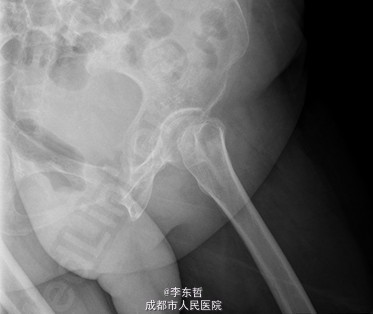

患者女,61岁,因“摔伤致左髋疼痛伴活动受限4+天”入院。患者自诉4+天前在浴室里不慎滑倒,左髋部着地,当时感左髋部剧痛,伴有活动受限,不伴有恶心呕吐、头痛头昏等不适。患者随即被家属送至当地医院,完善X线片后提示左股骨颈骨折,给予对症支持治疗后,患者家属为求进一步诊治,转至我院急诊科,以左股骨颈骨折送入我科。

查体:T:37.2oC,P:96次/分,R:22次/分,BP:113/62mmHg。神志清楚,无病容,皮肤巩膜无黄染,全身浅表淋巴结未见肿大。颈静脉正常。心界正常,心律齐,各瓣膜区未闻及杂音。胸廓未见异常,双肺叩诊呈清音,双肺呼吸音清,未闻及干湿啰音及胸膜摩擦音。腹部外形正常,全腹柔软,无压痛及反跳痛,腹部未触及包块,肝脏肋下未触及,脾脏肋下未触及,双肾未触及。双下肢无水肿。专科查体:视:双下肢不等长,左下肢外旋畸形,左髋肿胀,周围皮肤未见红肿,溃疡,窦道,瘘管等形成;触:双下肢皮肤感觉正常,末梢循环良好,足背动脉可扪及,左髋肿胀,触压痛明显,股骨颈叩击痛阳性,未闻及骨摩擦音及摩擦感;动量:双下肢肌力及肌张力正常,右髋、双膝、踝关节活动度良好,左下肢较右侧缩短约2cm,左髋因疼痛拒动。 辅助检查X片示:左股骨颈骨折,远断端向上方错位,左髋关节在位。骨盆骨质疏松。

积极完善术前检查及准备后行左股骨颈骨折闭合复位DHS内固定术